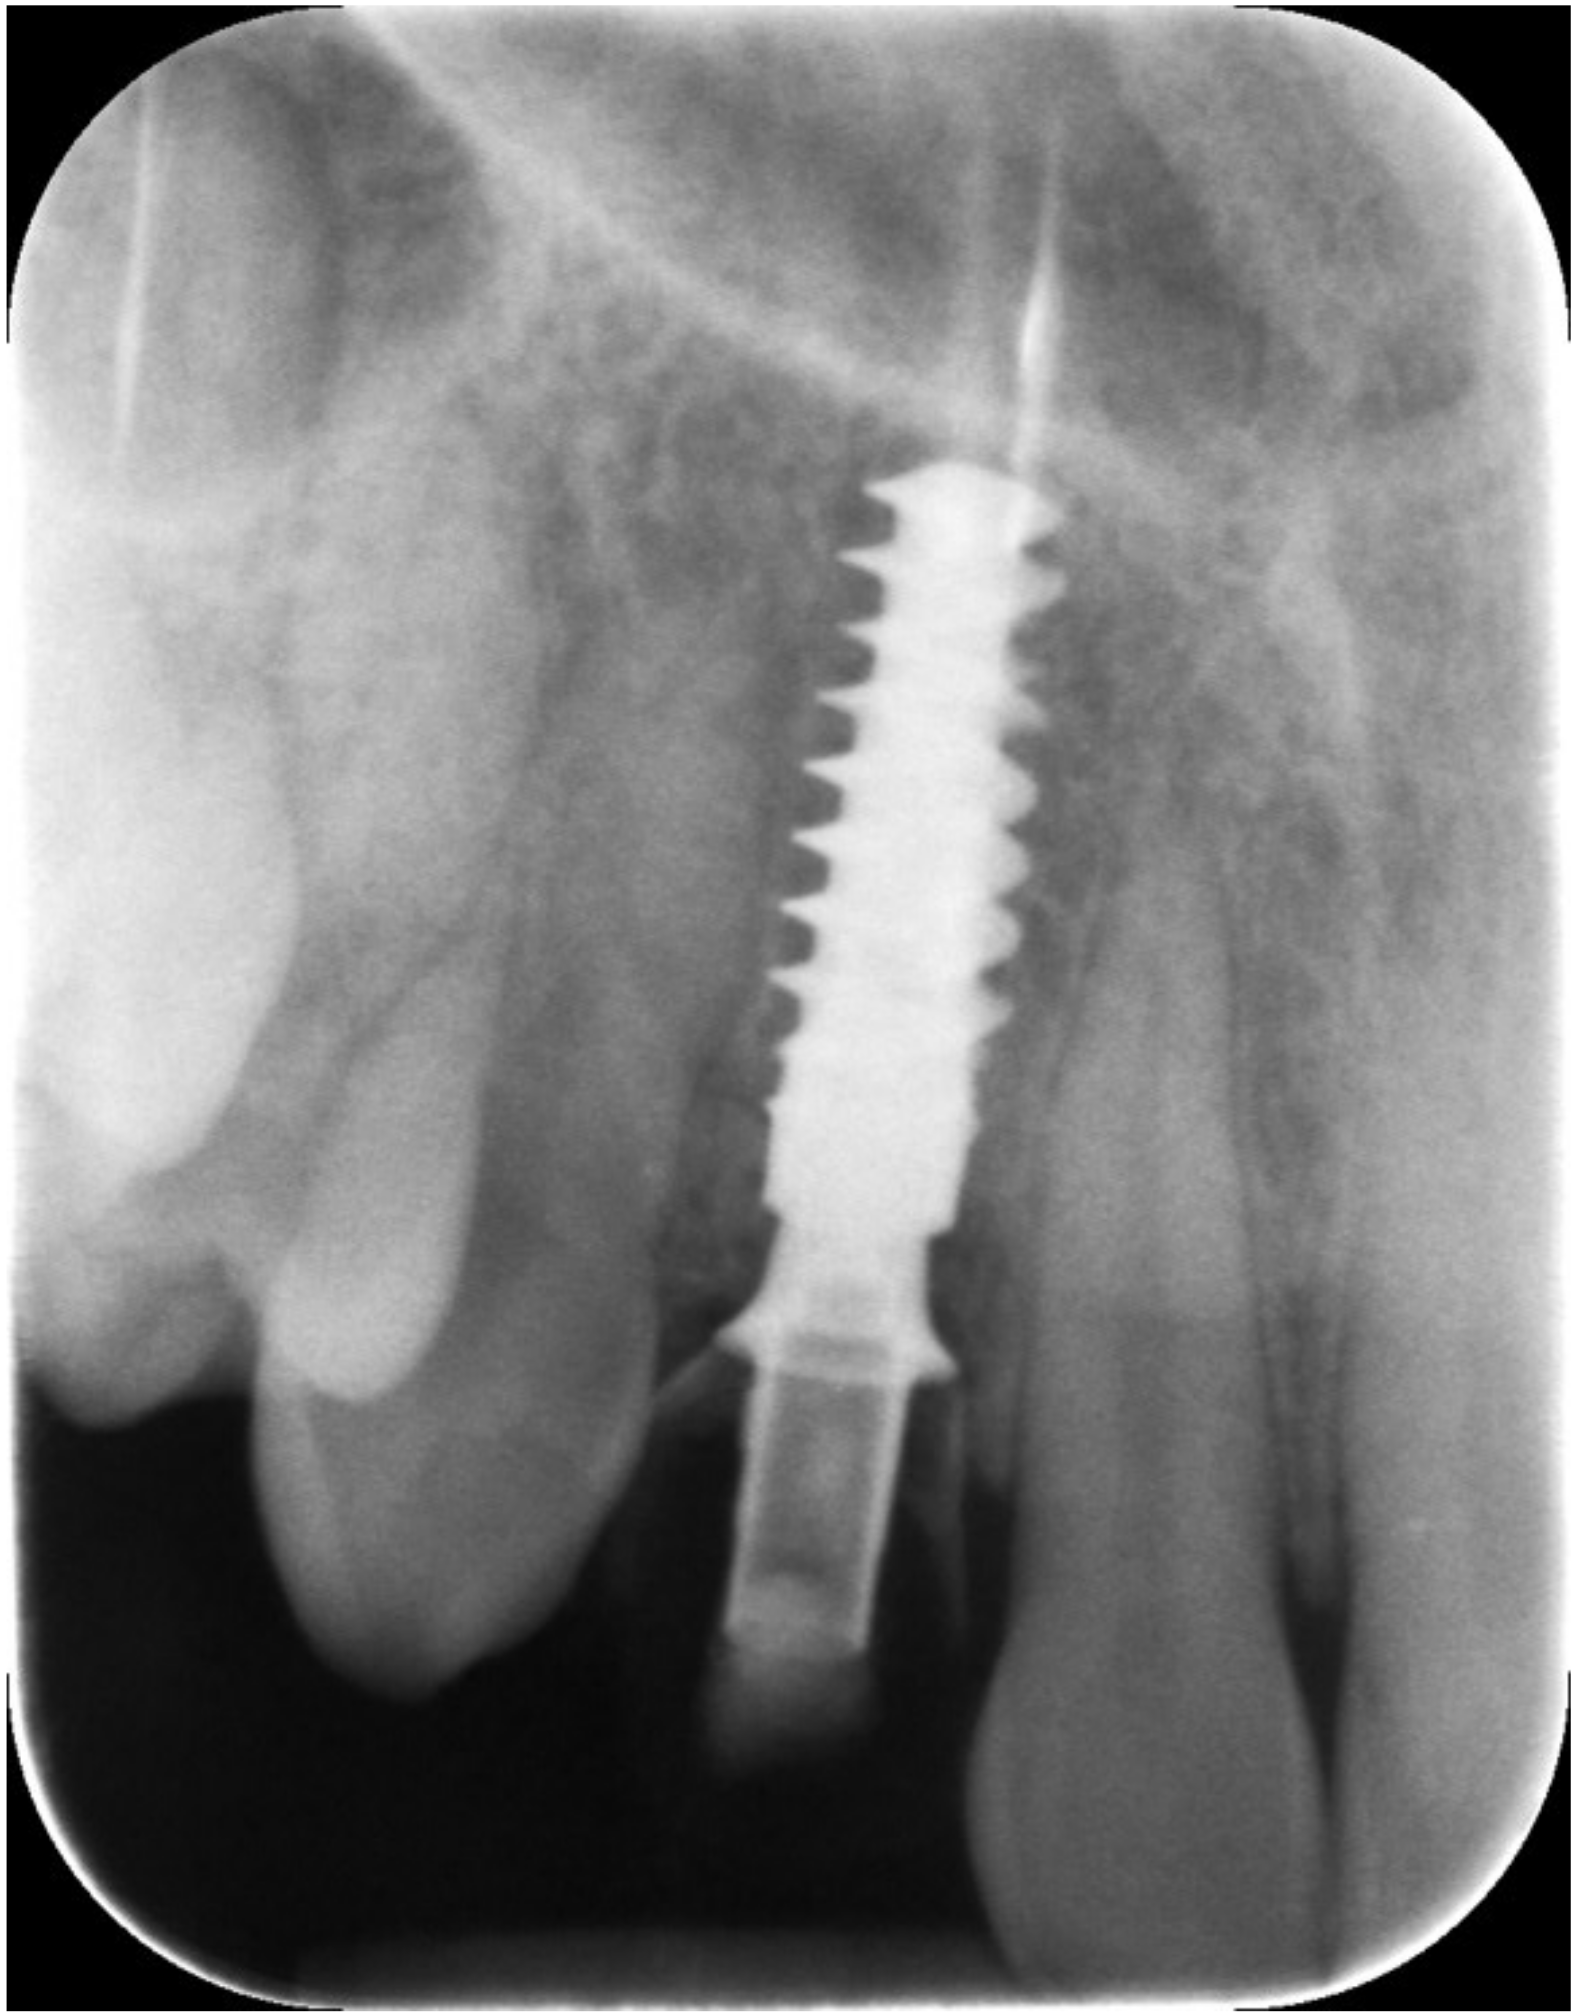

Figure 5.

Periapical X-ray at immediate temporization.